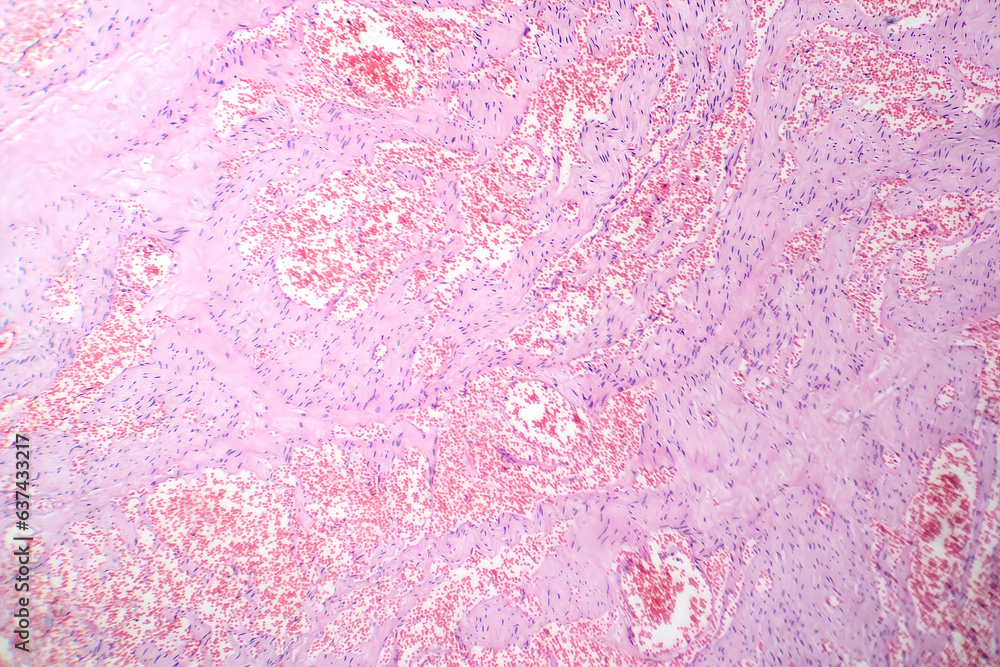

Histología

Consiste en acúmulos de células endoteliales en dermis o en tejido subcutáneo (a veces en ambos). Se diferencia del hemangioma cavernoso por una disposición más superficial y una mayor proliferación endotelial.